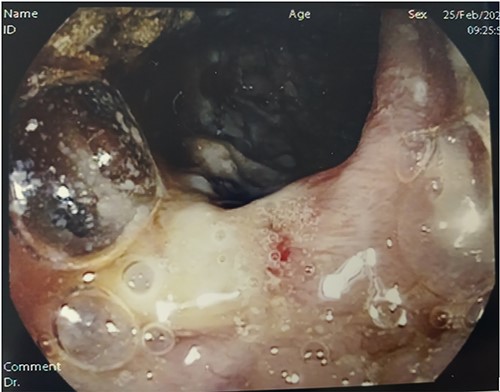

An entero-MRI was carried out, which highlighted another intestinal loop thickened. The patient then got a lot worse. She was in septic shock (102/66 mmHg and, 108 bpm) and hyperventilating; she had acute abdomen with a positive Blumberg sign and was tachypnoeic with 95% oxygen saturation. Surgeons were consulted and indication for exploratory laparotomy was given considering the clinical picture of sepsis and initial haemodynamic instability. Although the patient was preparing for surgery, Quantiferon-test result arrived with a positive result. At surgical intervention, abundant yellowish peritoneal effusion was found and sent to microbiological examination. The right colon was markedly altered and fibrotic, with multiple mesenterial nodes and miliary whitish granular dissemination on the right colon visceral peritoneum and peritoneal right-side wall. At 20-cm proximal to ileocecal valve, a hard and fibrotic lesion infiltrating the same ileal loop near the valve and a 20–30 cm further ileal double stricture were observed. The macroscopical presentation was more compatible with ITB than with CD or cancer. The bacterial translocation sepsis caused by TBC, which produced a severe right colon subversion therefore it was an absolute surgical emergency. Hence, a right hemicolectomy (Fig. 3, panel A) was performed. An ileal resection using the ileal stumps for a temporary loop ileostomy was preferred for the ileal stricture due to the clinical severity and the uncertain diagnosis, as an alternative to strictureplasty. A mesenteric lymph node sent to microbiological examination resulted positive on PCR for Mycobacterium tuberculosis, confirming ITB (Fig. 3, panel B and Fig. 4, panel A).

Operating pieces. Panel A shows right colon with a subverted mucosa; in particular, the blackish color indicates a suffering and ischemic mucosa. Panel B shows dissected pathological lymph node on which TBC diagnosis was made.